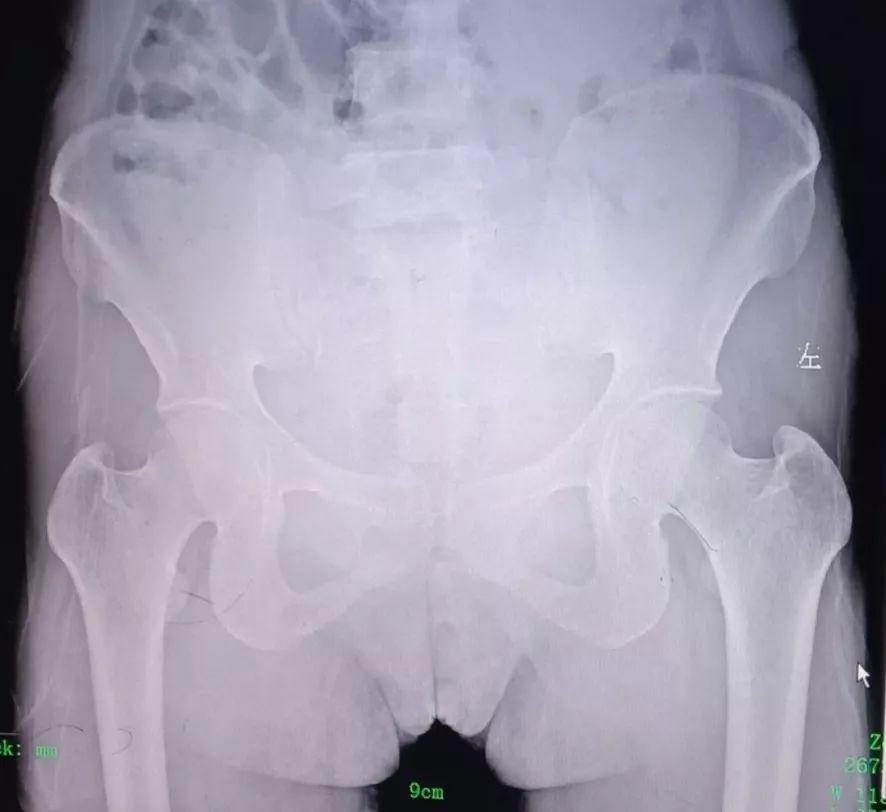

而弹簧现在已经发生了体内融合,被阴道宫颈部组织包埋。医师在对孕妇进行妇科检查时,仅能触摸到部分弹簧金属,通过拍片定位发现弹簧约有5*2.6cm长。

经细致讨论、反复评估后,妇产科手术医师决定邀请外科医师协助手术,使用克氏钳把弹簧逐个剪断取出,最终成功取出了7个小金属圈。